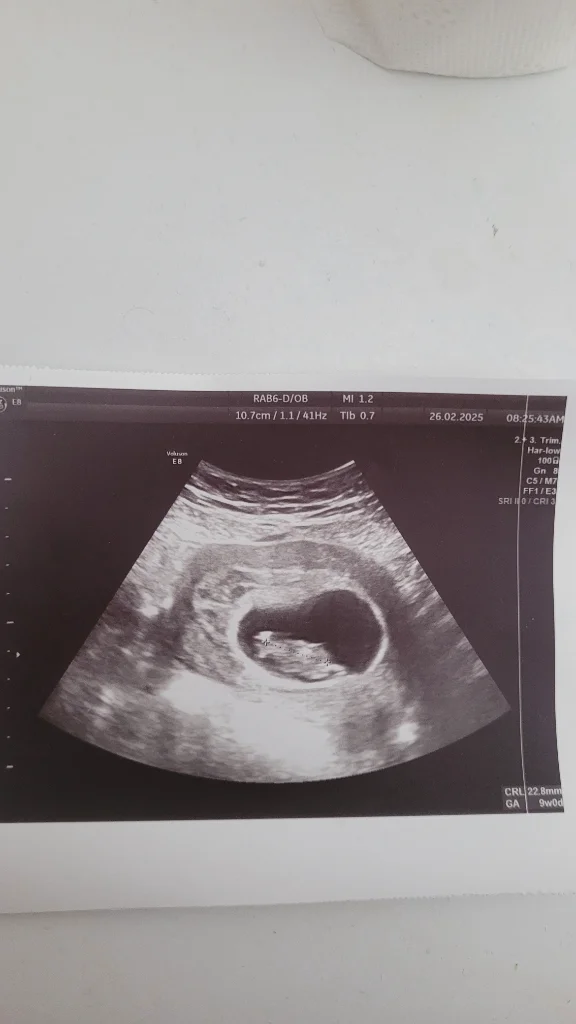

S sinemozay Yeni Üye Kayıtlı Üye 20 Şubat 2025 9 0 1 32 1 Mart 2025 Konu Sahibi Konu Sahibi xnadia99 #72 Tahminlerinizi alabilir miyim kızlar Eklentiler 1000032006.webp 66,1 KB · Görüntüleme: 27